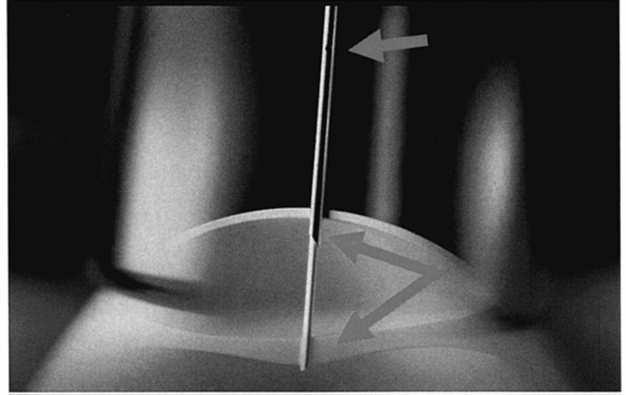

如图3所示,采用双针头方法可以穿透蛋壳。

此方法包含多项关键特性,使其成为注射鸡蛋的最优方式。

我们希望递送疫苗的针头与穿透蛋壳的针头分开,以最小化细菌携带或潜在污染的风险。

外针和内针具有不同的斜面设计:一个专门用于刺穿蛋壳,另一个则专门用于递送疫苗(见图4)。

图3:展示‘针中针’刺穿蛋壳和绒毛尿囊膜的鸡蛋注射过程

较大的针头用于刺穿蛋壳,它有四个小孔(上箭头所示),这些小孔允许液体清洁和消毒针头内部和外部,以及内注射针头的外部。这种内外针头的消毒有助于减少乃至几乎消除任何蛋与蛋之间的污染

图4:‘针中针’的图形描述

在另一幅图示(图4)中,可以看到‘针中针’的设计。

我们使用16号针头以30度斜角穿透蛋壳,并使用20号针头以45度斜角递送疫苗

这种设计使得疫苗递送非常精确。